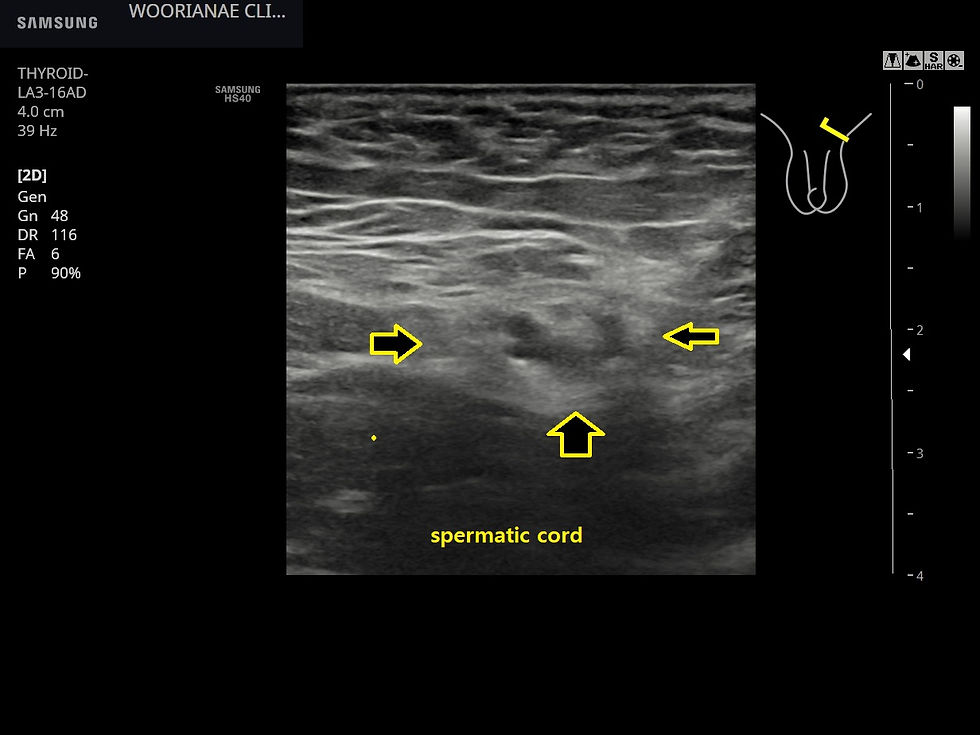

탈장의 관점에서 양측 서혜부를 관찰하였으며 헷갈릴 수 있지만 정삭 (spermatic cord) 이 양측에 약간 볼록하게 나와 있으나 대칭적으로 주행하는 것을 확인하였다. 정삭을 따라 혹은 hasselbach triangle에 뚜렷한 탈장 소견은 관찰되지 않았다.